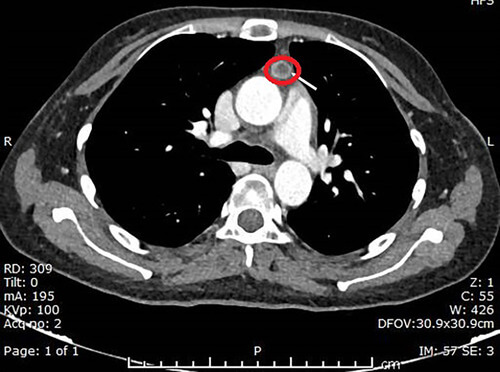

Die Spurensuche geht weiter mittels CT-Scans von Brust, Bauch und Becken - erfolgreich, denn es zeigt sich ein kleiner neuroendokriner Tumor des Thymus, der mit einer bilateralen Nebennierenhypertrophie einhergeht.

Die 24-jährige Patientin unterzieht sich daraufhin einer Exzision der mediastinalen Masse. In der anschließenden pathologischen Untersuchung des resezierten Gewebes zeigt sich ein gut umschriebener Tumor, der sich scharf vom umgebenden atrophischen Thymusgewebe abgrenzt.